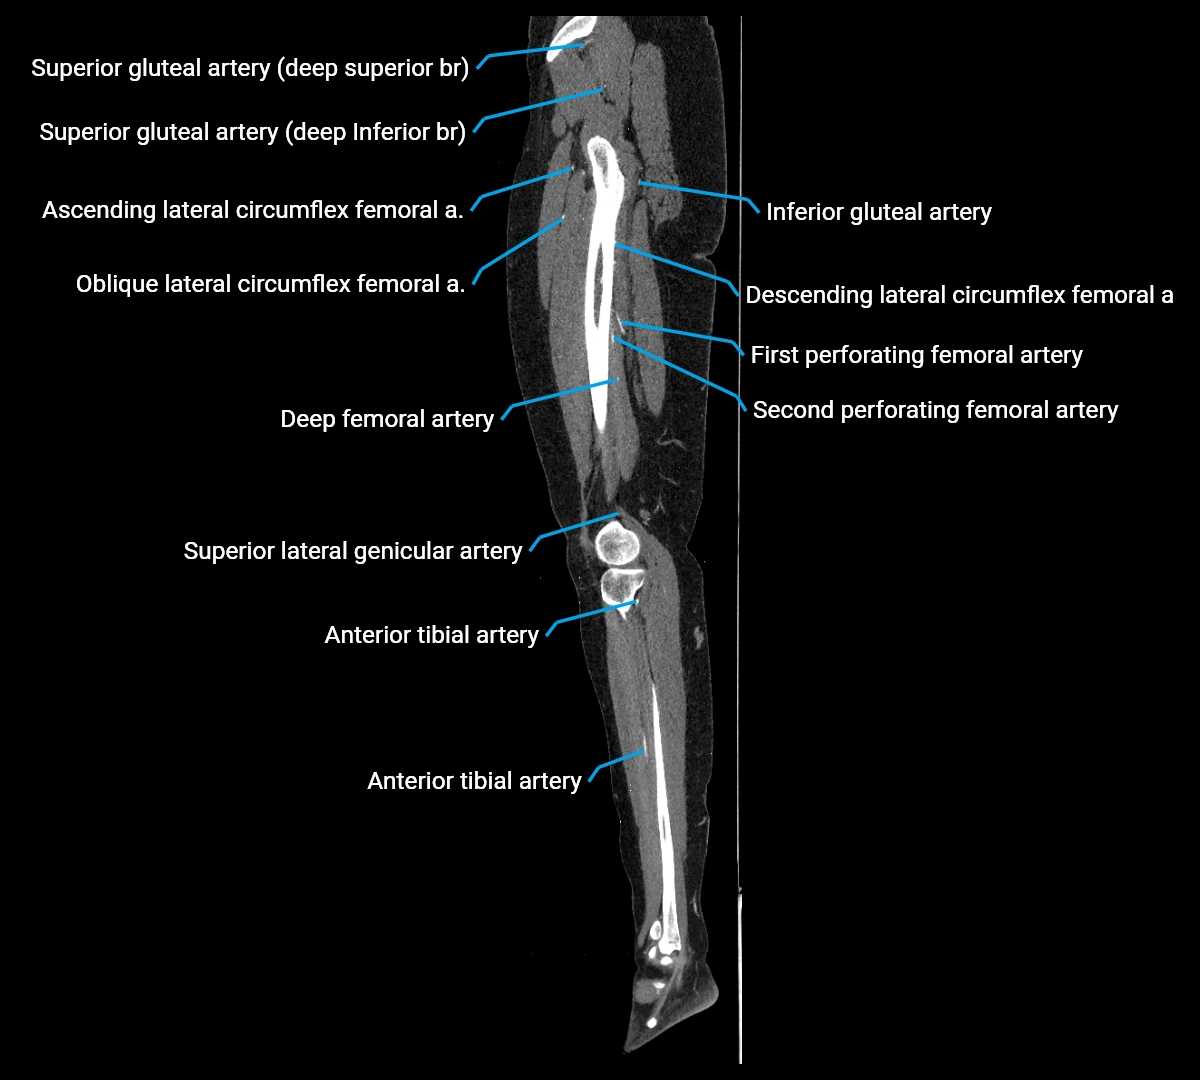

Contrast-enhanced CT (CTA):

• Gold standard for abdominal aortic imaging

• Provides excellent detail of lumen, wall, aneurysm, thrombus, and branch vessels

• Multiplanar and 3D reconstructions help in aneurysm measurement, stent graft planning, and dissection evaluation

• Detects acute rupture, traumatic injury, or occlusion with high sensitivity